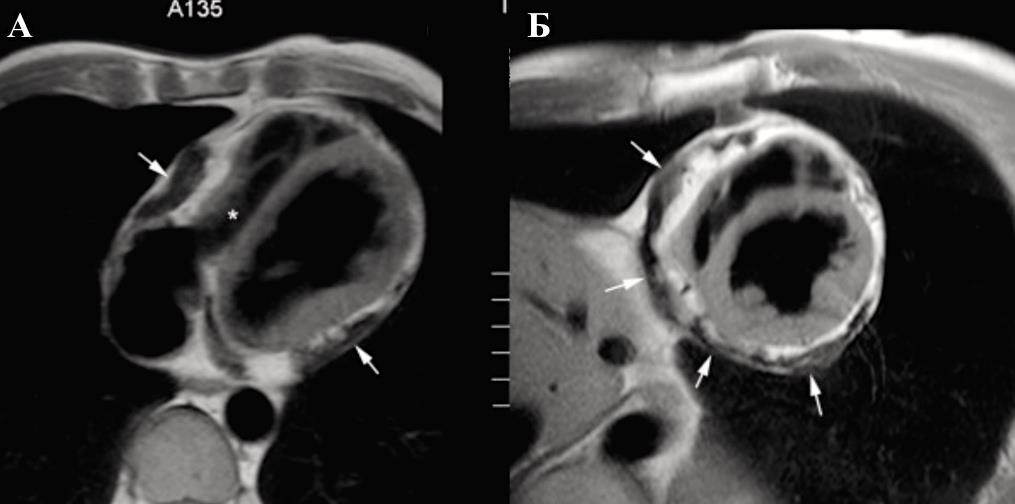

Высокая разрешающая способность КТ играет важную роль в дифференциальной диагностике констриктивного перикардита и рестриктивной кардиомиопатии. Выявляемое утолщение париетального листка перикарда в среднем от 4 до 20 мм позволяет разграничить эти состояния [153]. Однако у 28% (18% при аутопсии) больных с констриктивным перикардитом не определяется утолщение перикарда [154].

Кальцификация перикарда, выраженная в той или иной степени, визуализируется у 50% пациентов. При этом КТ позволяет, в отличие от ЭхоКГ, визуализировать отложение кальция на любой поверхности сердца, особенно в местах с большим содержанием эпикардиального жира (атриовентрикулярные борозды и основание сердца) (Приложение А3, рис. 11) [154, 155].

Констриктивный перикардит характеризуется утолщением перикарда, которое больше выражено со стороны правого желудочка и передней атривентрикулярной борозды (Приложение А3, рис. 12) [156].

В случаях констриктивного перикардита выявляются значительное утолщение перикарда, между листками которого обнаруживаются спайки c очагами казеозного перерождения и превращения в рубцовую ткань. Также возможно обнаружение обызвествления околосердечной сумки.